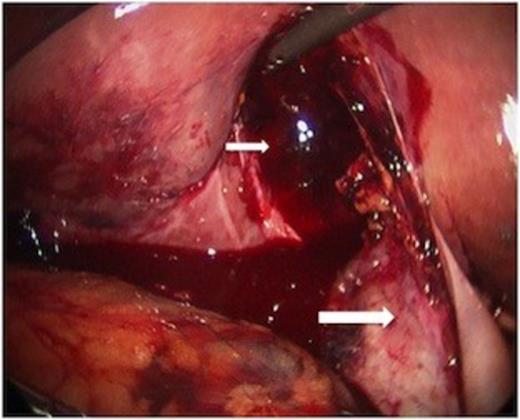

The body of the gallbladder was perforated on its inferior surface (arrow).